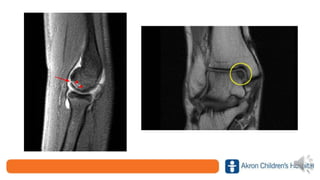

• Treatment

– Radiographs

• Typically negative but may show

Segund fracture

– Immobilization, protected weight bearing

– Prompt referral!

• We will see as a same-day

appointment or within a couple days

• We will obtain prompt MRI

– Surgical management plus PT and

activity restrictions (9 months)

• Non-operative treatment leads to

functional instability, secondary

meniscal/cartilage damage, and

likely early osteoarthritis

• Treatment – Radiographs •Typically negative but may show Segund fracture – Immobilization, protected weight bearing – Prompt referral! • We will see as a same-day appointment or within a couple days • We will obtain prompt MRI – Surgical management plus PT and activity restrictions (9 months) • Non-operative treatment leads to functional instability, secondary meniscal/cartilage damage, and likely early osteoarthritis